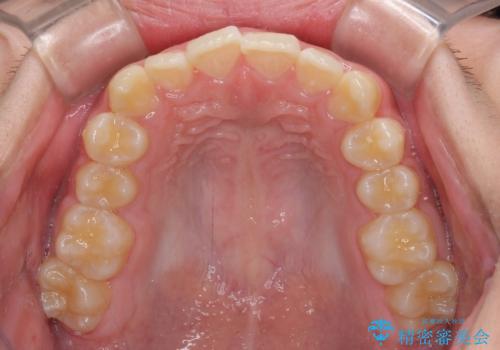

しっかり使って短期間で治療 インビザラインによる叢生解消

- 上下前歯のデコボコを気にして来院された患者様です。

「しっかりと装着する」が実行でき、高校3年生の秋には治療を終えることができました。